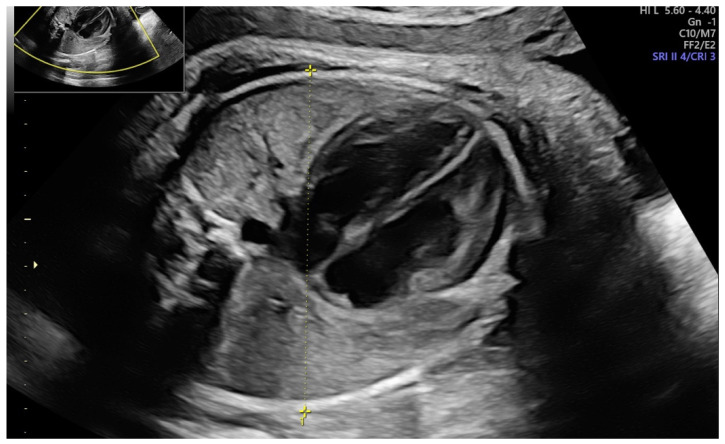

We performed a single-center prospective observational study at a tertiary-care university hospital from March 2021 to February 2022. Our Institutional Ethical Review Board had authorized the research design (protocol no. 0013626/i date: 3 May 2021), and all participating women submitted written consent after a detailed discussion. We included all full-term pregnancies (37–42 weeks) accepted for the delivery. We excluded pregnancies with antepartum hemorrhage, fetal growth restriction, stillbirths, multiple gestations, breech position, uterine or congenital malformations. In addition, the complete history with age, parity, past miscarriages, body mass index (BMI) and any medical illnesses was recorded for each patient. The fetal diameters were assessed utilizing a Voluson E8 (General Electric Medical Systems, Zipf, Austria) or a Samsung HS70 (Samsung Medison, Seoul, South Korea) with a transabdominal convex probe (3.5–5.5 MHz). To reduce the bias, all ultrasound scans were conducted only by two expert sonographers (M.L.V. and M.M.) (equipped with the Fetal Medicine Foundation certificate of competence in the 11–13-week scan) who performed all the ultrasonographic examinations of enrolled women [28]. We recorded the main fetal ultrasonographic parameters: biparietal diameter (BPD), head circumference (HC), abdominal circumference (AC), femur length (FL) and amniotic fluid index (AFI). Estimated fetal weight (EFW) was calculated using the Hadlock 4 formula [29]. We also registered two additional parameters: the mid-arm diameter measured by placing the caliper from skin to skin on the upper arm near the heart (Figure 1) and the transverse thoracic diameter (TTD) estimated by determining a transverse section of the fetal chest at the level of the heart (four-chamber view) (Figure 2).

Figure 2.

Transverse thoracic diameter (TTD) estimated by determining a transverse section of the fetal chest at the level of the heart (4-chamber view).